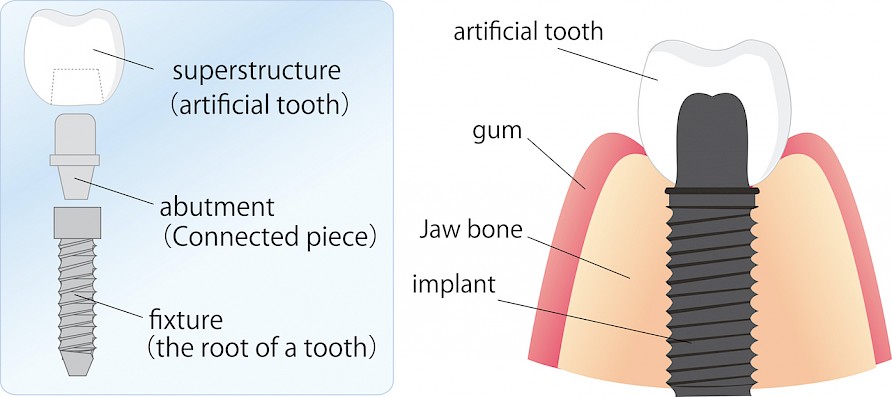

There are two main parts to an implant. The main part of the implant is the post. This part goes into your jaw where it fuses with the bone. Posts are usually made from titanium. This material is known for its durability and hypoallergenic qualities. Zirconia, which is metal-free, can also be used to make implant posts, in the rare instances the patient is allergic to titanium.

The top part of the implant is called the crown. This is the part that looks like your natural teeth. Similar to a regular dental crown, these can be made from a variety of materials. Porcelain, ceramic and metal crowns are all potential options. Porcelain can also be fused to metal for a stronger implant crown.